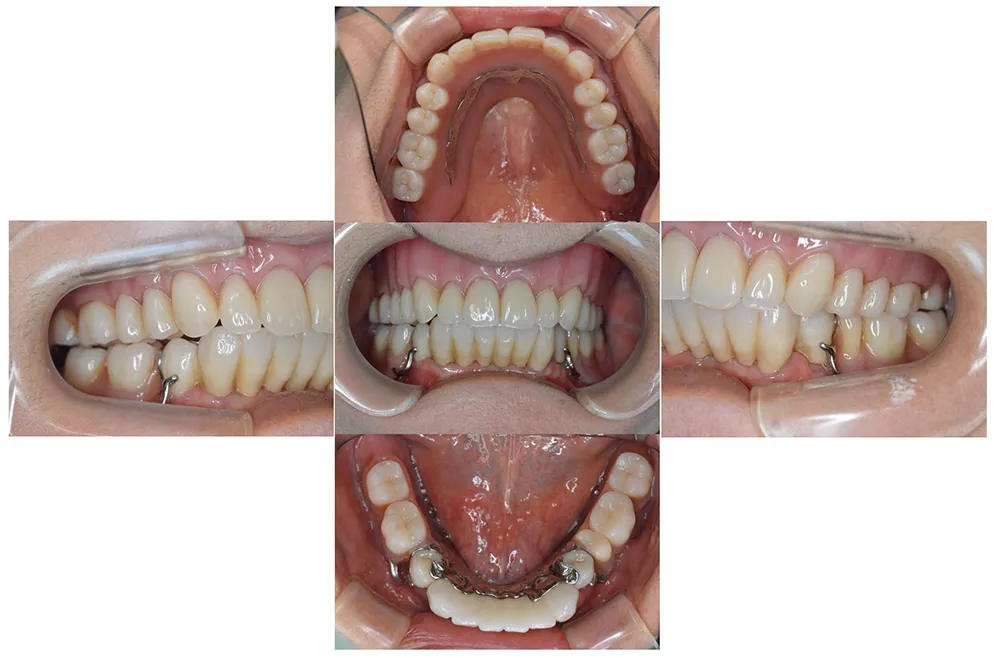

インプラント治療及び補綴治療のケース

■治療前:奥歯が無いため噛み合わせが深く下の歯が全く見えない

噛み合わせが低いため全体的に歯が削れている

■治療後:下顎 左下5・6番、右下4・6番にインプラント治療

その他の歯に補綴治療をしたことにより、奥歯もしっかりと咬むことができ、奥歯ができたことにより噛み合わせも上がって下の歯も見えるようになり、審美的にも改善された

| 主訴 | 歯科治療をしても歯がすぐに欠けてしまう 奥歯が無いため、奥歯で咬めない |

| 治療方法 | インプラント治療 + 補綴治療 |

| 治療期間 | 約1年 |

| 通院回数等 | 約20回 |

| 費用 | 約250万円(税込) |

| リスク・副作用 | 術後の腫れ・痛み |